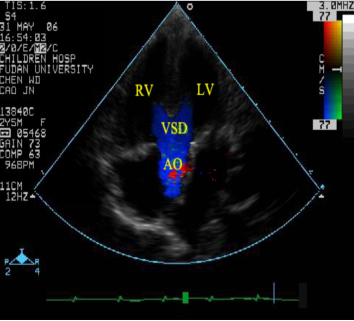

法洛四联症:超声心动图表现

室间隔缺损、主动脉骑跨

右室流出道狭窄

连续波多普勒测量右室流出道压差